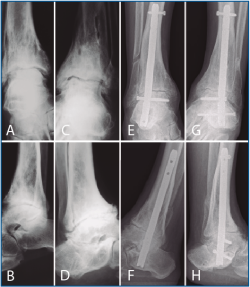

La segunda artrodesis se llevó a cabo durante el año siguiente a la primera intervención. La artrodesis fue tibioastragalina bilateral en 2 pacientes y tibiotalocalcánea (TTC) bilateral en el paciente restante. La estabilización ósea se realizó en un caso con 2 tornillos canulados Acutrak Plus® (Acumed, Hillsboro, EE. UU.) cruzados en ambos tobillos (Figura 1), en otro caso con clavo endomedular retrógrado T2 12 × 200 mm (Stryker, Schönkirchen, Alemania) en ambos tobillos (Figura 2) y en el último caso se utilizaron tornillos canulados Acutrak Plus® cruzados en el tobillo izquierdo y la técnica Putti en el tobillo derecho (Figura 3). La fijación de la artrodesis se realizó con el pie en plantígrado.

Figura 3. Caso 3. Varón de 77 años con artrosis bilateral de tobillo primaria. Radiografía lateral de tobillo derecho (A) y anteroposterior izquierdo (B) preoperatoria. Radiografía lateral de tobillo derecho que muestra una artrodesis tibioastragalina mediante técnica Putti con una consolidación parcial, asintomática, de la artrodesis y cambios degenerativos de la articulación subastragalina posterior pasados 21 meses de la intervención (C). En el tobillo izquierdo (D) se aprecia una artrodesis tibioastragalina mediante tornillos canulados cruzados del tobillo izquierdo con una consolidación parcial, asintomática, de la artrodesis al año y medio de la última intervención.